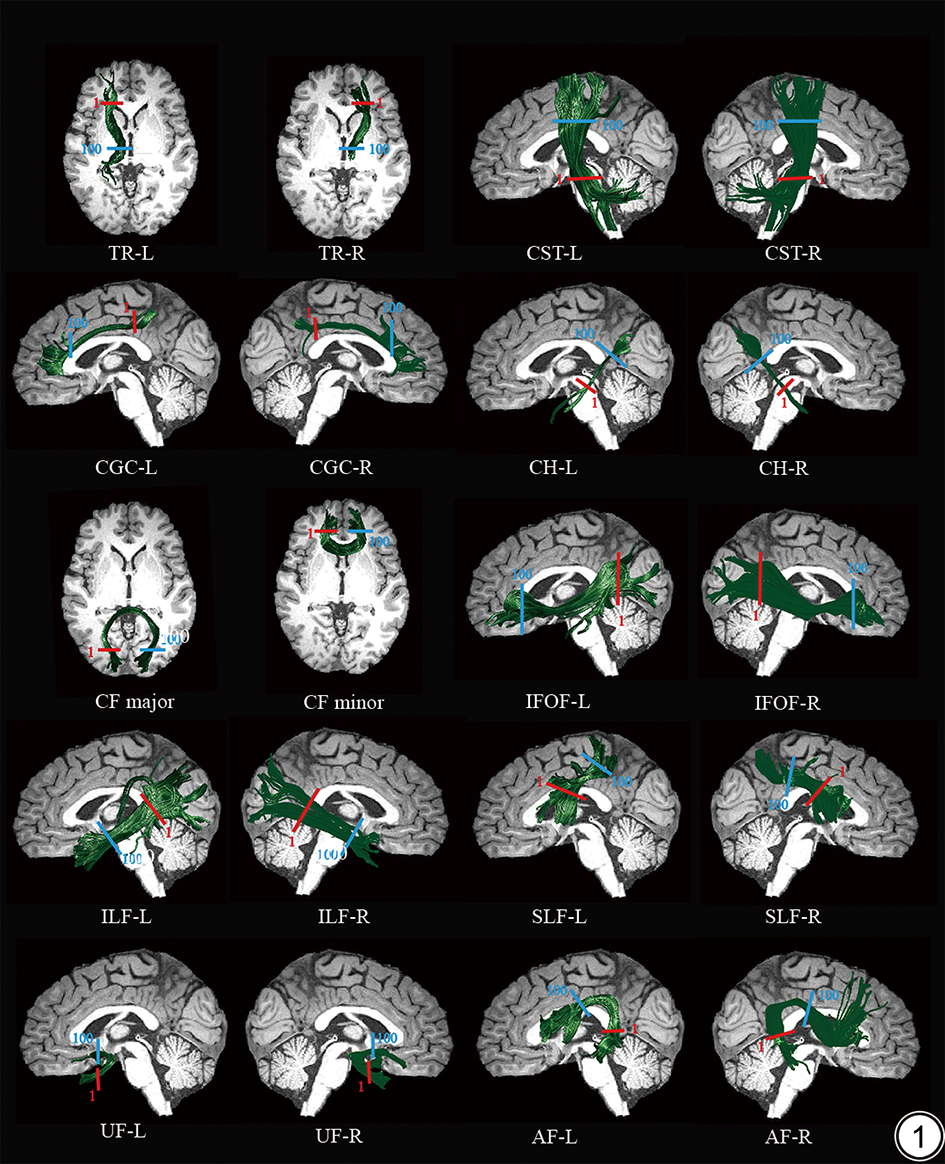

本研究中已识别的20条WM纤维束包括双侧丘脑辐射束、双侧皮质脊髓束、双侧扣带束、双侧海马旁扣带束、双侧额枕下束、双侧下纵束、双侧上纵束、双侧钩束、双侧弓状束以及胼胝体大钳和小钳,见图1

图1  AFQ追踪的20条白质纤维束示意图。红色实线是第一个节点,蓝色实线是第100个节点。TR:丘脑辐射;CST:皮质脊髓束;CGC:扣带束;CH:海马旁扣带束;CF major:胼胝体大钳;CF minor:胼胝体小钳;IFOF:额枕下束;ILF:下纵束;SLF:上纵束;UF:钩束;AF:弓形束;L:左;R:右。

Fig. 1  The identified WM fiber tracts by AFQ. The red solid line represents the first node, and the blue solid line represents the 100th node. TR: thalamic radiation; CST: corticospinal tract; CGC: cingulum cingulate; CH: Cingulum Hippocampus; CF major: forceps major of corpus callosum; CF minor: forceps minor of corpus callosum; IFOF: inferior fronto-occipital fasciculus; ILF: Inferior Longitudinal Fasciculus; SLF: superior longitudinal fasciculus; UF: uncinate fasciculus; AF: arcuate fasciculus; L: left; R: right.